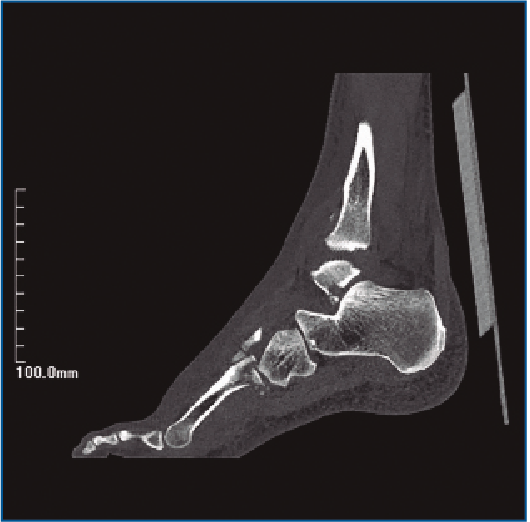

En la exploración destaca una inflamación y dolor en el borde externo del pie que no impide la deambulación. En la revisión de las pruebas complementarias (radiografía simple y TC) se confirman las lesiones previamente diagnosticadas, junto con una luxación del cuboides plantomedial (Figuras 1 y 2).

Figura 2. Imágenes de la tomografía computarizada (TC) que ponen en evidencia la fractura de la base del 4.º metatarsiano con la luxación plantar del cuboides.